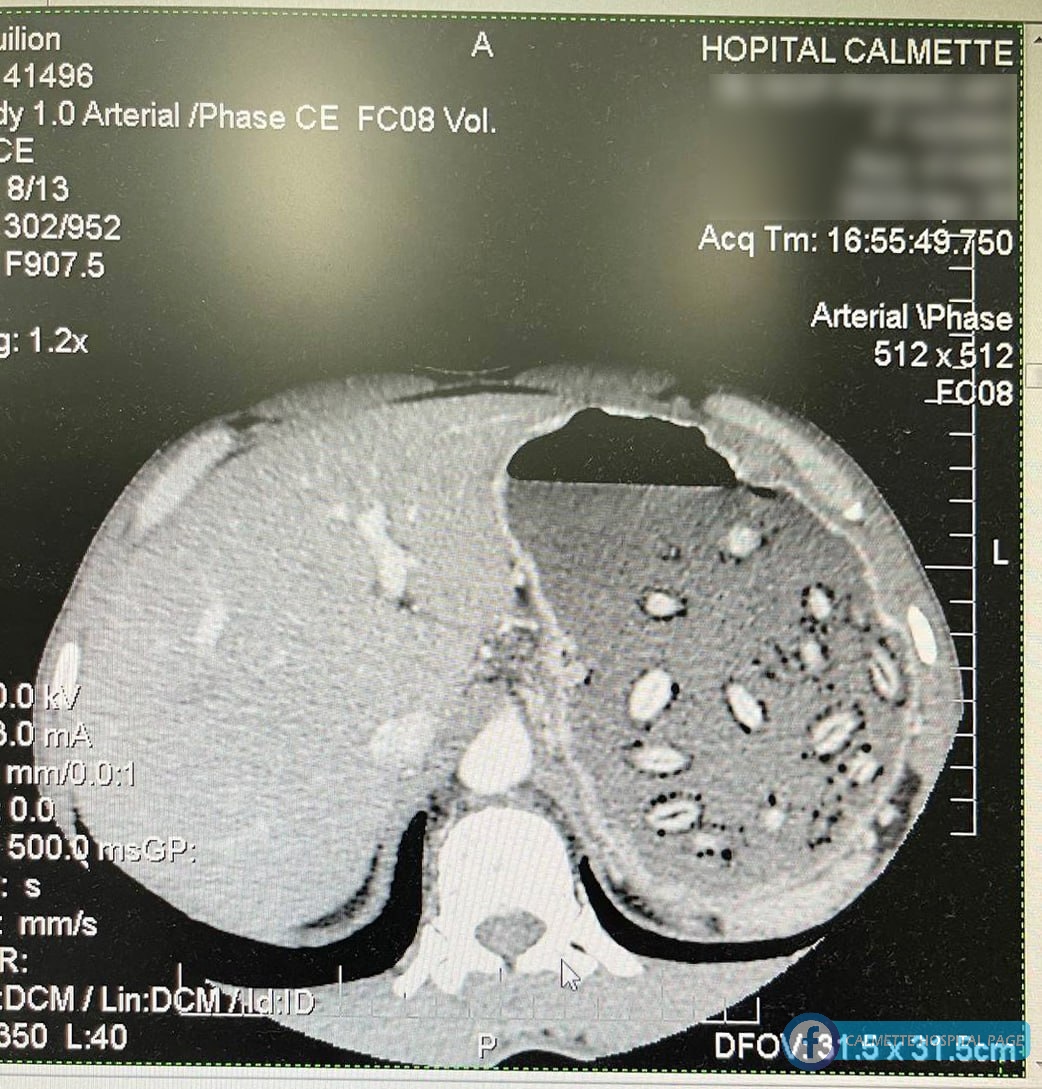

ក្រោយពីការសាកសួរពីគ្រូពេទ្យជំនាញយ៉ាងម៉ត់ចត់រួច គ្រូពេទ្យក៏បានស្នើរសុំធ្វើ អេកូពោះ និងស្កេនពោះ។ ជាលទ្ធផល យើងឃើញមានគ្រាប់ម៉ាក់ប្រាងមួយគ្រាប់ ជាប់នៅនឹងគល់ពោះវៀនតូច (Bulbe) ដែលជាមូលហេតុនាំឲ្យគ្រាប់ជាច្រើនផ្សេងទៀត ចាល់នៅពេញក្រពះ។

ក្រោយពីបានពិភាក្សាគ្នាយ៉ាងម៉ត់ចត់រវាង គ្រូពេទ្យឯកទេស ថ្លើម ក្រពះ ពោះវៀន និងគ្រូពេទ្យឯកទេស ថ្នាំសណ្តំ រួចមក យើងក៏សម្រេចចិត្ត ធ្វើការឆ្លុះក្រពះ ទាំងយប់ ដើម្បីចាប់គ្រាប់ទាំងនោះចេញ។ ក្រុមគ្រូពេទ្យបានព្យាយាមចាប់គ្រាប់ម៉ាក់ប្រាងទាំងនោះចេញម្តងមួយៗ បានដោយជោគជ័យ ដែលមានចំនួនសរុប ៧៣ គ្រាប់ ក្នុងរយៈពេលជិត ៣ម៉ោង។